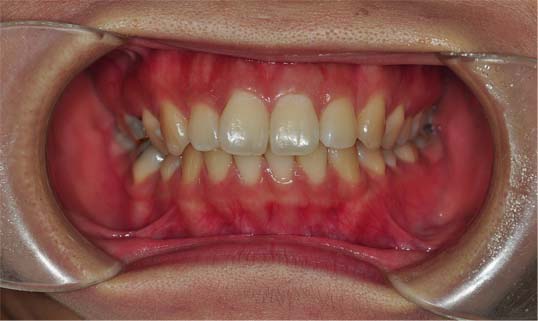

저는 치아가 덧니는 심하지 않기때문에 교정하기에 어렵지 않을거라 혼자 생각했는데 제가 잇몸과 치아 모두 돌출되어있고 어려운 케이스라고 하시더라구요 헝헝 (아래 사진을 참고해주세요~)